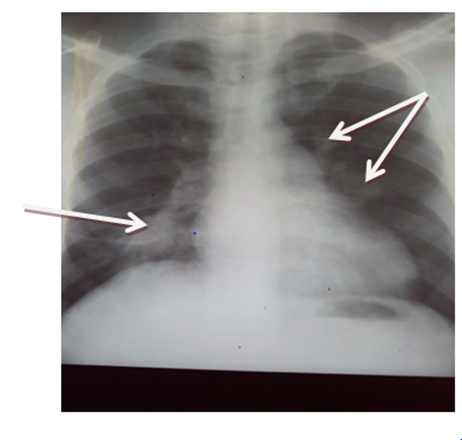

The results of laboratory investigation revealed packed cell volume (38%). Other cells counts were within normal limit but for the peripheral blood film that showed microcytes, macrocytes and anisocytosis. Chest radiograph showed widespread rounded opacities in both lung fields while constrast enhanced CT scan revealed bilateral multiple saccular dilatations of the pulmonary arterials in keeping. Sputum for acid and alcohol fast bacilli and Gene expert (negative), erthrocyte sedimentation rate (40mm/hr), Hepatitis screening (HBsAg, Anti-HCV were both negative), HIV rapid serology test (negative), and VDRL for Syphilis (negative). The values of Anti-Nuclear Antibody, pANCA, cANCA were within normal limit and pathergy test was negative after 48hrs.

Figure 3 Shows a contrast enhanced Chest CT of patient that revealed bilateral multiple saccular dilatations of the pulmonary arterial branches

Our index patient is a male in his fourth decade with recurrent oro-genital ulcers and uveitis. This is in tandem with the diagnostic criteria for BD as well as the archetypal chest CT finding of pulmonary artery aneurysm.7,10 The age of onset in our patient is higher than the 25years associated with poor prognosis, however, the gender as well as the evidence of pulmonary artery aneurysm has been associated with high mortality and morbidity.1